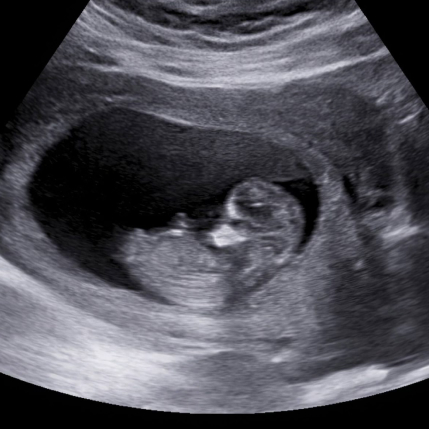

Developed in Canada by Synergyne ART Analytics, AIM uses advanced AI and machine learning to analyze ultrasound images with speed, accuracy, and consistency—helping fertility clinics make smarter decisions, faster.

AIM uses computer vision to interpret ultrasound images—removing subjectivity and delivering consistent, cycle-specific receptivity scores.

Submit an image, and AIM AI generates a receptivity score in near real-time. Results are reviewed by experts for accuracy and clinical confidence.

With enhanced 3D analysis and deep data extraction, AIM supports personalized embryo management and hormone protocols—all without additional patient burden.